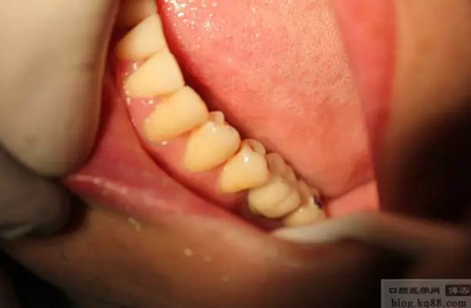

雙側(cè)種植牙分別做成連冠、前牙做成單冠,左下6、7連冠,(戴牙后照片)